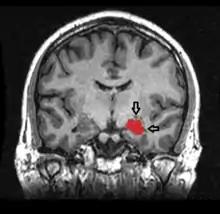

![]() El hipocampo está localizado en la parte medial del lóbulo temporal del cerebro. En esta vista lateral del cerebro humano, el lóbulo frontal está a la izquierda, el lóbulo occipital a la derecha, y los lóbulos temporal y parietal han sido retirados en gran medida para revelar el hipocampo subyacente. | ||

Se trata de una estructura marginal y de estructura de capas más sencilla de la misma sustancia gris cortical del lóbulo temporal. Por ello pertenece, por una parte al sistema límbico y por otra a la arquicorteza, componiendo junto al subículo y el giro dentado la llamada formación hipocampal. Al igual que el resto de la corteza cerebral es una estructura pareada, con dos mitades que son imágenes especulares en ambos hemisferios cerebrales. Tanto en humanos como en otros primates, el hipocampo se localiza en el interior de la parte medial o interna del lóbulo temporal, bajo la superficie cortical. La forma de caballito de mar es típica de primates, pero en otros mamíferos tiene formas variadas, como la del plátano.